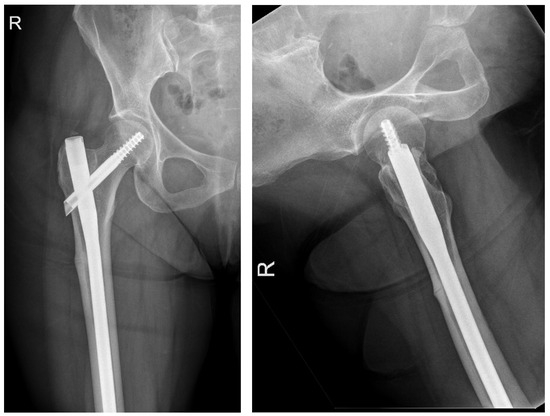

The following radiographs present the initial radiographs from the day of injury along with those obtained during the final OPD follow-up of the patient. The sequence presents radiographs demonstrating full radiological union (Scheme 1 and Scheme 2) and X-rays with no evidence of fracture healing at the final OPD follow-up (Scheme 3 and Scheme 4).

Scheme 2. X-ray of right femur AP view (left) and lateral view of right hip (right) of atypical subtrochanteric fracture—September 2024 (radiological union).

Jcm 14 02858 sch002